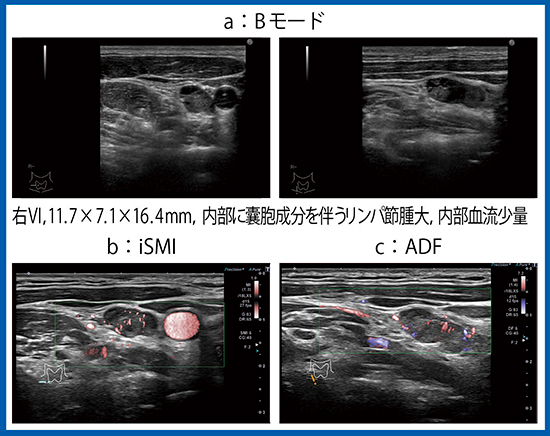

症例6は甲状腺乳頭癌術後4年目の精査である。内部に囊胞成分を伴うリンパ節腫大があり(図12 a),iSMI(図12 b)とADF(図12 c)にて内部に少量の血流が認められ,リンパ節転移であった。

図12 症例6(19歳,男性):甲状腺乳頭癌のリンパ節転移